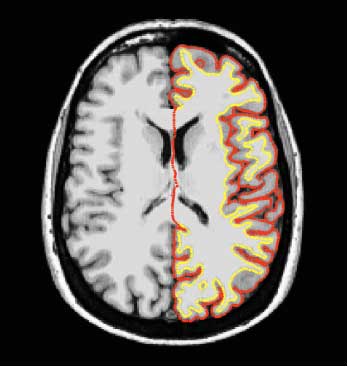

Naučnici Univerziteta u Cirihu, ustanovili su da sklonost ka altruizmu zavisi od količine sive materije u mozgu.

Naučnici Univerziteta u Cirihu, ustanovili su da sklonost ka altruizmu zavisi od količine sive materije u mozgu.

Ispostavilo se da je kod onih, kod kojih u prostoru između parijetalnog i temporalnog režnja mozga ima više sive mase, veća verovatnoća da će podelili novac sa nepoznatom osobom.

Istraživači su otkrili da je kod cicija aktivnost u tom delu mozga veoma intenzivna čim se i najmanja količina novca nađe u igri, dok se kod altruista to područje aktivira samo kada je reč o velikim svotama.

Ciriški naučnici su, takođe, ustanovili da postoji razlika u količini sive materije, te da je kod škrtica ona manja nego kod darežljivih osoba.